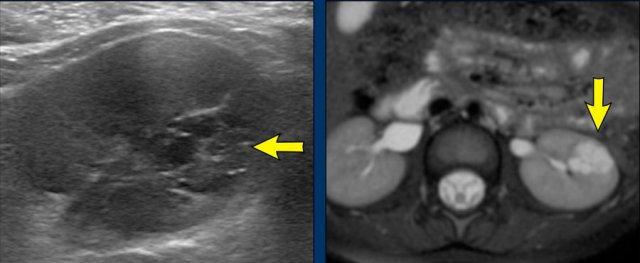

Hình ảnh

Siêu âm và MRI của bé trai bốn tuổi với tổn thương dạng nang đa thùy ở vùng cực giữa thận trái (mũi tên).

Tổn thương được phát hiện tình cờ khi bé được chín tháng tuổi. Trong quá trình theo dõi, không ghi nhận sự thay đổi nào. Tổn thương phù hợp với u thận dạng nang, một tình trạng lành tính.

Tổn thương tương tự được quan sát trên ảnh chuỗi xung T2W mặt phẳng ngang.